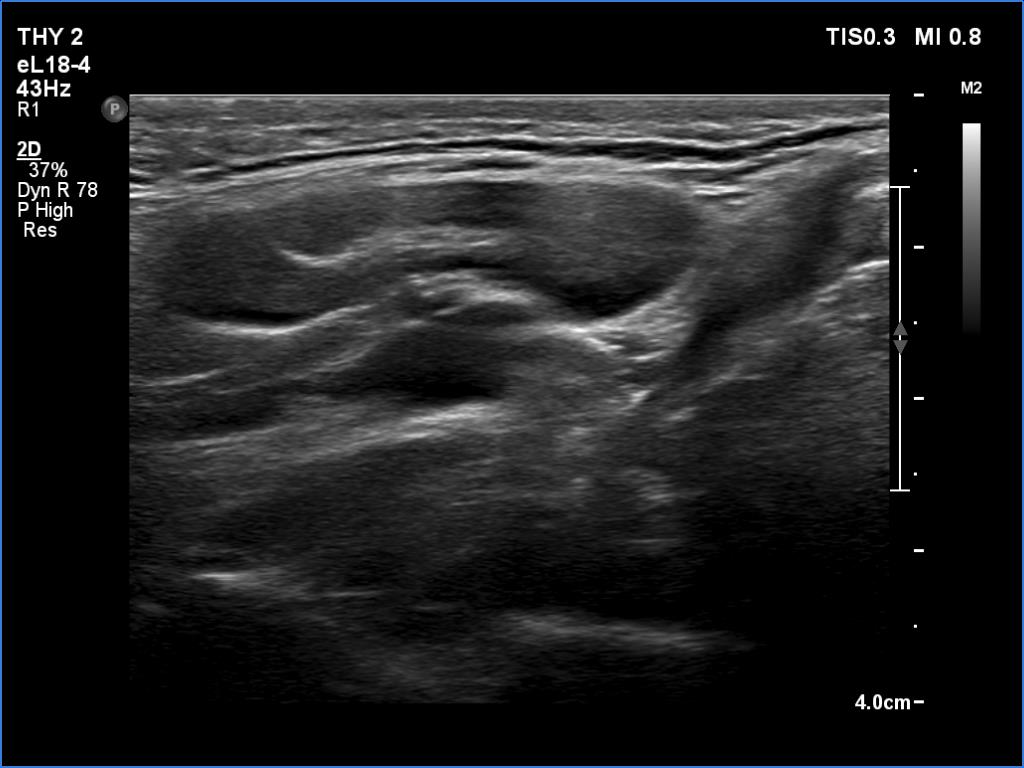

Ultrasonography revealed hypoechoic discrete lesions in both thyroid lobes. The lesions presented microcalcifications. Corresponding to the palpable mass in the right submandibular region, a reactive-type regular lymph node was found. There was an enlarged lymph node in the left submandibular region. The node had a regular hilum but displayed a heterogeneous pattern.

Comment. Until the final histological examination is completed, I would like to draw attention to two things. One is the heterogeneity of the left lymph node and the other is the size and structure of the lesions in the thyroid beds - these features are suspicious of thyroid cancer.